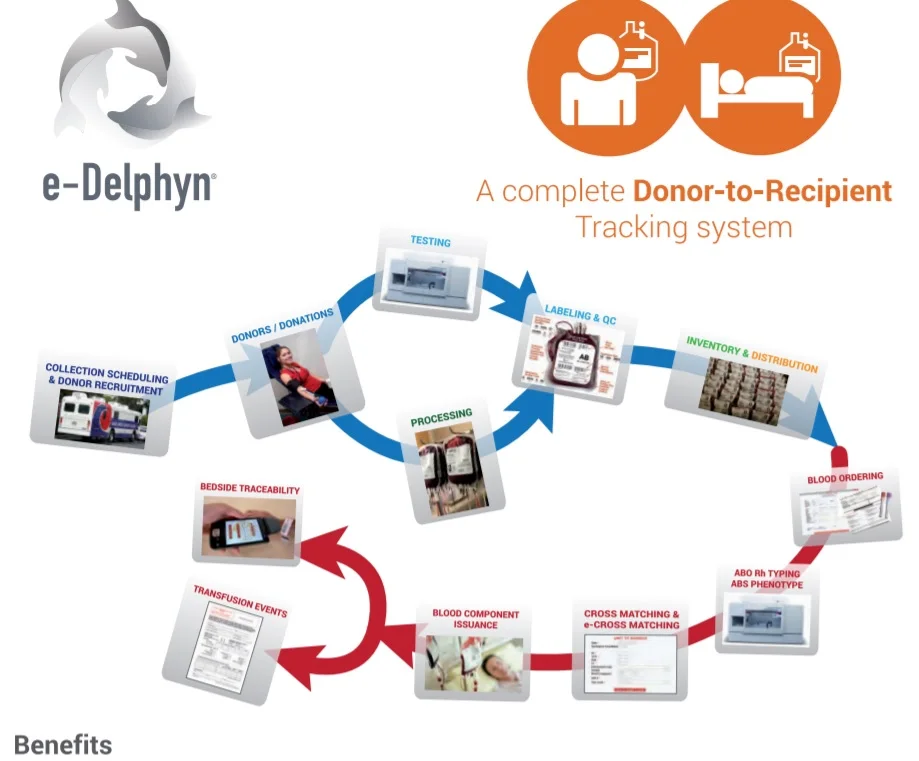

Blood Bank Software Managment

- Category:

- Supplier: Centre,de,Services,D,Informatiques,SARL [Mauritania]Centre,SARL

RUB 1,826,402.40

In Stock